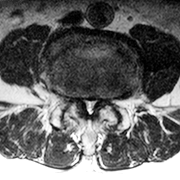

MRIによって神経の圧迫の程度がわかります。

術前のMRI横断像:硬膜管は高度に狭小化している |